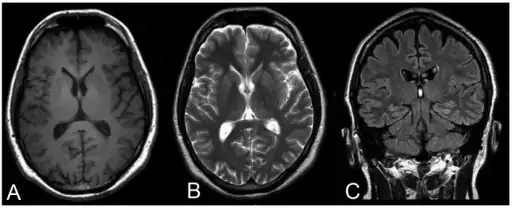

Progressive myoclonic epilepsy type 1-a,b) MRI c) FLAIR